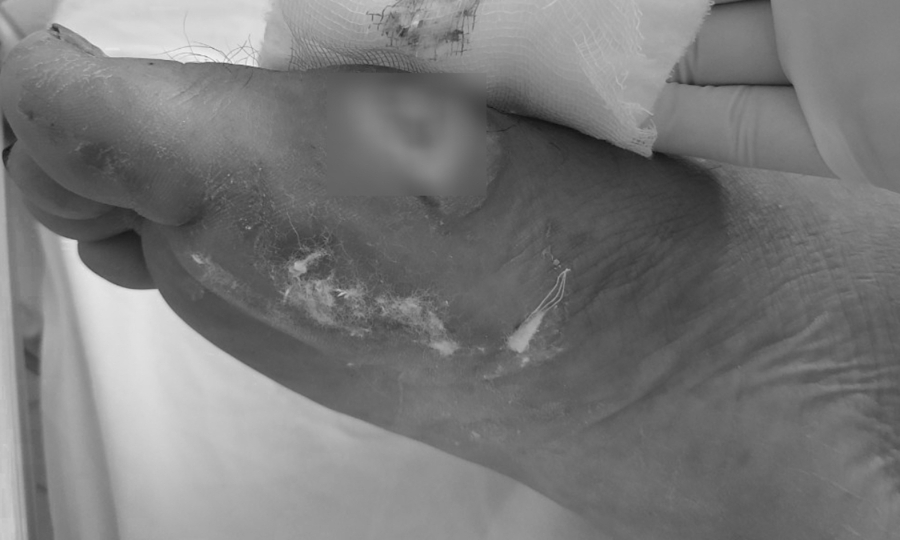

Chân bệnh nhân bị hoại tử do vi khuẩn Burkholderia. Ảnh: Bệnh viện cung cấp.

Sau đợt mưa bão kéo dài từ đầu tháng 10 đến nay, nhiều trường hợp mắc bệnh Whitmore đã gia tăng ở nhiều tỉnh miền Trung. Quảng Trị ghi nhận 24 ca, Bệnh viện Thừa Thiên-Huế tiếp nhận 30 ca … Bệnh viện Đà Nẵng điều trị 29 ca, bệnh nhân chủ yếu đến từ Quảng Nam, Nghệ An, Quảng Ngãi và Đà Nẵng. – Vết thương do áp xe do Whitmore gây ra đã được điều trị. Ảnh: Bệnh viện cung cấp.